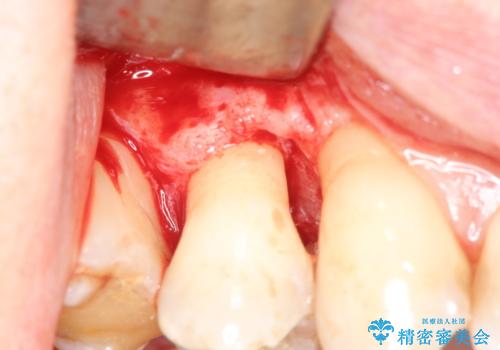

部分矯正を含む 歯周病治療 (再生治療・歯周ポケット除去・MTM・連結補綴)

検査の結果、強い歯ぎしりによる歯の周囲の骨の吸収が認められたため歯槽骨の再生・歯周ポケットの除去・力に対抗する連結補綴・補綴前処置としての小矯正を計画します。

今回連結補綴を行うにあたり、歯周病の問題を解決するために再生療法・歯周ポケット除去手術を、またより歯の神経を保存し力に対抗できる環境を整えるために小矯正を行い精度の高いメタルボンドクラウンを製作することができました。